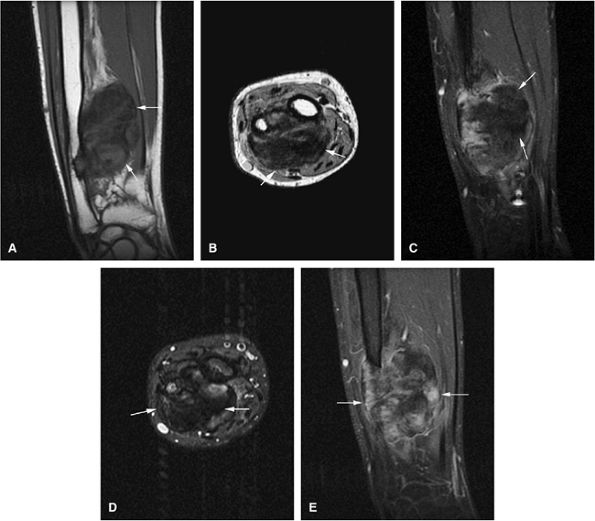

FIGURE 14-93 ● Primary lymphoma of bone involving the distal femur. (A) Coronal T1-weighted images show low-signal-intensity lymphomatous marrow replacement crossing the physeal scar and involving the subchondral bone. (B) An extraosseous soft-tissue component is present on the axial T1-weighted image (arrows). (C) This sagittal proton density-weighted image demonstrates lymphomatous involvement of intermediate signal with associated soft-tissue component (arrows). On (D) sagittal and (E) axial fat-suppressed T2-weighted fast spin-echo images, the tumor is of intermediate signal and hyperintense compared to adjacent bone marrow. Associated soft-tissue mass (arrows) and surrounding bone marrow edema (black arrowhead) are noted. (F) Coronal and (G) axial contrast-enhanced fat-suppressed T1-weighted images show enhancement of the tumor with nonenhancing areas (arrows) representing necrosis.

Distinguishing primary lymphoma of bone from secondary involvement is important because the latter has a worse prognosis and is treated differently.